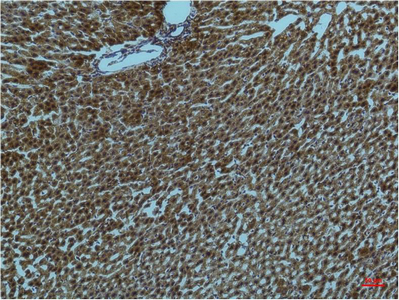

Immunohistochemistry analysis of paraffin-embedded rat Liver Tissue using PI3 Kinase p85 alpha antibody.High-pressure and temperature Sodium Citrate pH 6.0 was used for antigen retrieval.

Immunohistochemical analysis of paraffin-embedded Human tonsils using PI3 Kinase p85 alpha antibody.High-pressure and temperature Sodium Citrate pH 6.0 was used for antigen retrieval.